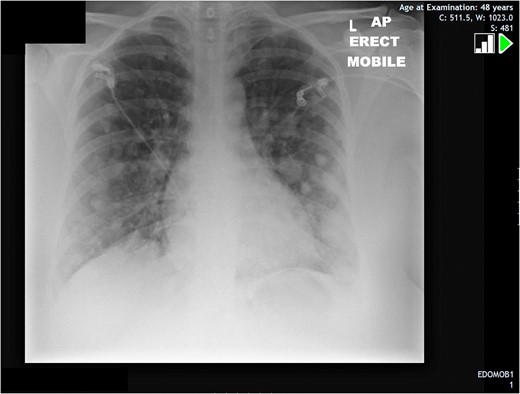

A 48-year-old lady was discovered to have multiple pulmonary nodules on chest x-ray (Fig. 1) which was taken in view of desaturating levels of oxygen post-operatively. The patient had undergone elective left leg varicose vein surgery. An urgent CT scan was subsequently booked and showed innumerable soft tissue lesions throughout both lung fields including a sub-pleural individual lesion measuring 3.5 cm in the lingula (Fig. 2). One lesion in the right upper lobe contained a small amount of air due to possible local erosion into an adjacent airway. Furthermore, a para-tracheal mass was seen on the right side measuring 5.6 cm with appearances suggestive of pleural metastases. Mediastinal nodes were reported as slightly prominent on the scan with nodes at the right hilum up to 12 mm in size.